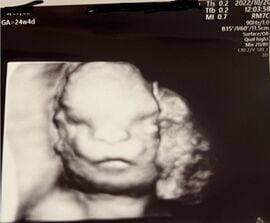

異常が見つかったのは、妊娠22週で行った中期スクリーニング検査のときだった。そして24週で大学病院に転院。医師から告げられたのは、耳慣れない症状だった。

「頭部を上から見た際に頭蓋骨がレモン型に変形している」「個人差と言えないレベルに目が離れている」「鼻の骨が短い」「下顎がすごく小さい」

しかし、医師にもそうなっている原因はわからない。エコーで見る限り、見た目の異常以外は元気に育っているとのことでホッとしつつも、しほさんは症状から推定される病気をインターネットで鬼のように検索しては不安を募らせていった。